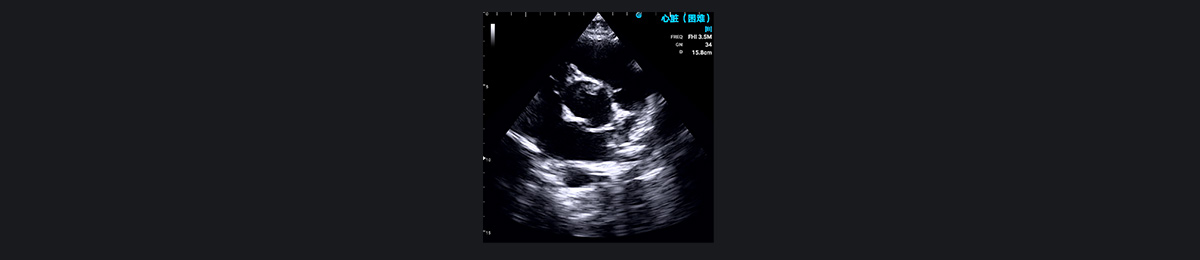

¶ÔÓÚ¼±ÐÔÐØÍ´µÈΣ¼°ÉúÃüµÄÐØÍ´×ÛºÏÕ÷£¬SonoEye ¿ÉÒÔÌṩ¹Ø¼üµÄÐÄÔàÕï¶Ï£¬ÉîÈëÁ˽â°êĤÎÊÌâ¡¢Ðİü¼²²¡»òÔ·¢ÐÔÐļ¡×´¿ö¡£Ëü¶ÔÓÚÆÀ¹ÀÒÉËÆ¼±ÐÔÐ£ËÀ»¼Õߣ¨ÐĵçͼȷÈÏǰ£©¡¢ÑªÁ÷¶¯Á¦Ñ§²»Îȶ¨»¼ÕßÒÔ¼°ÑÏÖØ·Î˨Èû»¼Õ߷dz£ÓмÛÖµ¡£Ê¹Óà SonoEye ½øÐÐ×ۺϳ¬ÉùÐĶ¯Í¼¼ì²é¿ÉÒÔÆÀ¹ÀÖ÷¶¯Âö¼Ð²ãµÄ·¶Î§ºÍ²¢·¢Ö¢£¬Ñ°ÕÒÐİü»òÐØÇ»»ýÒº£¬²¢²âÁ¿Ö÷¶¯Âö¸ù²¿µÄÖ±¾¶¡£

¶þ¼â°êÏÁÕ¡¢×óÐÄ·¿Ö×Áö¡¢×óÐÄË¥½ß¡¢·ÊºñÐÔÐ¡¡¢Ðİü»ýÒº»òËõÕÐÔÐİüÑ×ÒÔ¼°ÑÏÖØµÄ·Î˨ÈûµÈÇé¿ö¾ù¿Éµ¼ÖºôÎü¶Ì´Ù»òºôÎüÀ§ÄÑ¡£Ê¹Óà SonoEye ÊÖ³Öʽ³¬Éù²¨¿ÉÒÔÓÐЧÕï¶ÏÕâЩ²¡Ö¢¡£

Ðİü»ýÒº